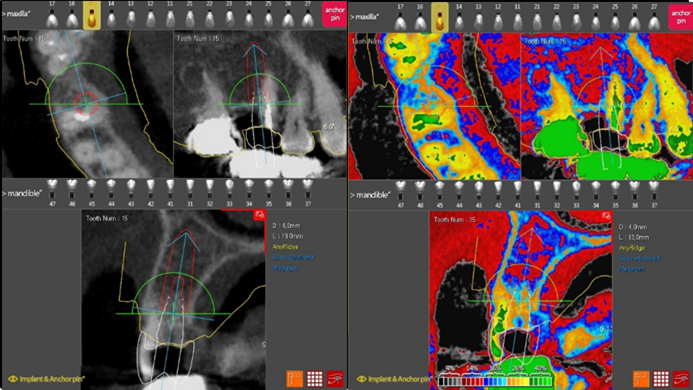

Dr. Kwang Bum Park, digital guided surgery, bone regeneration, maxillary posterior, #13, #14, guided surgery, GBR, AnyRidge, i-GEN, Mega-Oss, R2GATE, R2GATE Full surgical kit